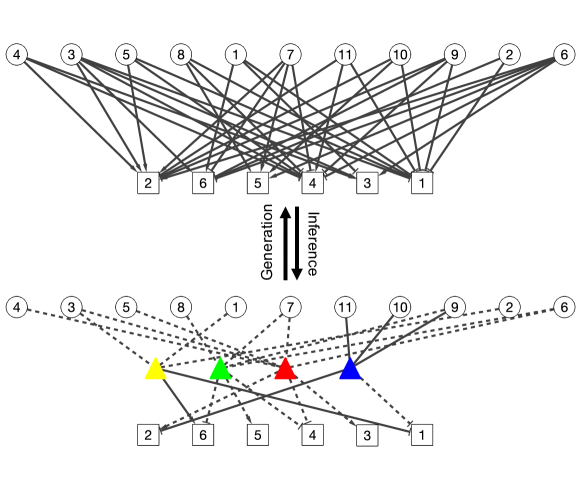

Edge-labeled random networks. DFA can be also interpreted as inference for a random network with labeled edges. The observed categorical matrix is treated as a categorical adjacency matrix which encodes a bipartite random network. Patients form one set of nodes and symptoms form another set. The edge labels correspond to the categories in . See the bipartite network on the upper portion of Figure 4 where the two labels (, ) are respectively represented by arrow heads and flat bars. DFA assumes that the observed bipartite graph is generated from a latent tripartite graph (given in the lower portion of Figure 4). Inference under the DFA model reverses the data generation process. The tripartite graph introduces an additional set of (latent) nodes corresponding to diseases. The edges between patients (symptom) and diseases indicate PD (SD) relationships. Prior PD and SD knowledge is represented by fixing the corresponding edges (solid lines in Figure 4).